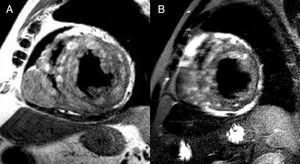

The patient was asymptomatic. Echocardiography provided limited information because of a poor acoustic window. Cardiac magnetic resonance imaging showed left ventricular dilation with severe systolic dysfunction. The right ventricular free wall presented a 30x40-mm lesion. The wall of the left ventricle was infiltrated by small lesions (Figure 1) that were hyperintense on gradient-echo sequences and T1- and T2-weighted images (Figure 2A); application of a fat-suppression pulse did not reduce the intensity of the signal (Figure 2B). Areas of late gadolinium uptake were observed in both ventricles (Figure 3). Endomyocardial biopsy did not provide diagnostic data because the lesions had not infiltrated the subendocardium. At 1 year following the diagnosis, the patient remained asymptomatic and was receiving angiotensin-converting enzyme inhibitors.

Figure 2.

Although a histopathological diagnosis was not available, the magnetic resonance pattern was typical of melanotic tumors. Schwannomas are tumors of neural origin rarely found in the heart. Although surgical treatment has been reported for local forms, the usual management approach is conservative. In melanotic forms, a differential diagnosis should be established with metastasis of melanoma.